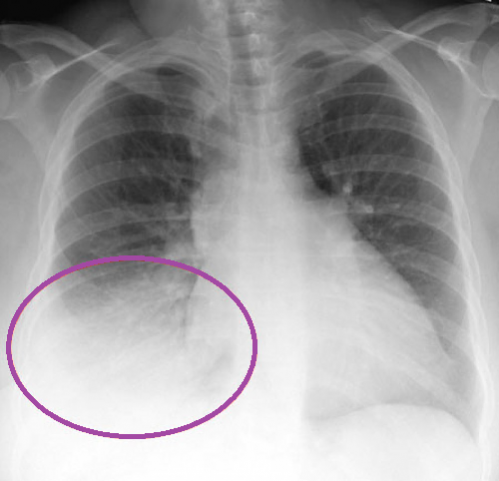

Оптимальным способом дифференциации обструктивного бронхита от воспаления легких является рентгенография. Зачастую ее вполне достаточно, и не приходится прибегать к дополнительной лабораторной диагностике. Если же на рентгеновском снимке картина заболевания недостаточно ясна, назначается бронхоскопия, МРТ и другие исследования.

Еще проводят рентгенографию – обычно на снимке ясно различаются признаки воспалительного процесса, характерного для пневмонии.

При бронхите на снимке контур бронхиального дерева становится более чётким, усиление лёгочного рисунка свидетельствует о наличии воспалительного процесса.

При обследовании лечащий врач обнаруживает хрипы в бронхах. Они могут определяться с одной стороны или иметь двусторонний характер. При подозрении на острый бронхит, и также воспаление легких, врач назначает дополнительное обследование-рентген. На снимке бронхит выглядит как «усиление легочного рисунка». Бронхиальное дерево лучше просматривается и определятся.

Опытный врач знает, как отличить острый бронхит от пневмонии. При прослушивании врач наблюдает изменения в виде хрипов и прослушиваются они локально, в зоне воспаления. Хрипы при бронхите отличаются равномерным расположением. При подозрении на пневмонию врач назначает рентгеновское обследование. На снимке воспаление легких видно, как затемненные участки с четкими границами. Пневмония может поражать от 1/3 до 2/3 всего легкого.

Как отличить бронхит от пневмонии по результатам рентгеновского снимка

Несмотря на некоторые различия пневмонии и бронхита, нередко клиника бывает размытой. В такой ситуации для установления верного диагноза необходимо сделать флюорографию или рентгенографию – это наиболее достоверный способ диагностики. По результатам рентгенограммы лечащий врач сможет легко распознать болезнь. Худшие опасения подтвердятся, если на снимке будут отчётливые затемнения.

| Рентгенографическая картина | инфильтрат (как правило, в нижней доли легкого), расширение корней | усиление легочного рисунка |